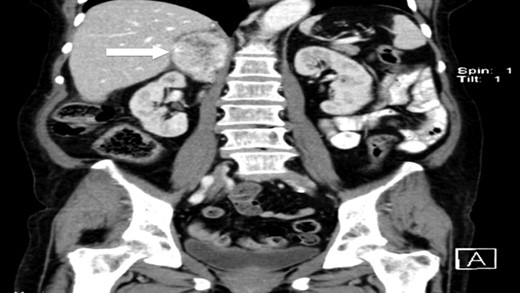

The authors report a case of a 64-year-old female, with no relevant family history and a past medical history of recently diagnosed supraventricular tachycardia, arterial hypertension, type 2 diabetes mellitus, euthyroid multinodular goiter and chronic venous insufficiency. She was referred to our Institution from other Hospital where she went due to paroxysms of palpitations, headache and diaphoresis, that led to biochemical investigation that was remarkable for: total plasmatic cathecolamines: 73 747 ng/L (normal range (NR) <598 ng/L), plasmatic noradrenaline: 73 589 ng/L (NR <420 ng/L), adrenaline: 130 ng/L (NR <84 ng/L), plasmatic dopamine: 28 ng/L (NR <94ng/L), aldosterone: 87,5 ng/dL (NR 4–31 ng/dL), plasmatic renin activity: 33 ng/mL/h (NR 0,5–4 ng/mL/h), Vanylmandelic acid: 39,2 mg/24 h (NR <13,6 mg/24 h). Abdominal contrast enhanced CT scan revealed a large (70 × 35×78 mm3), hyperdense (20 HU) right adrenal mass. Abdominal magnetic resonance (MRI) also described an adrenal mass with 66×33 mm2, suggestive of pheocromocitoma (slightly hypointense on T1 and markedly hyperintense on T2 weighted imaging). No vascular nor locoreginal lymph node involvement were found and the left adrenal was radiologically normal. The patient underwent genetic testing with next generation sequencing, that excluded mutations of the succinate dehydrogenase (SDHB, C, D and A), MEN2, VHL, Neurofibromatosis type 1 genes. Genetic testing for MAX and TMEM127 were not performed due to institutional unavailability. Pre-operative pharmacological therapy was initiated with phenoxybenzamine (10 mg twice a day), followed by bisoprolol (20 mg/day) and amlodipine (5 mg/day), which rendered the patient fit for surgery. The patient underwent transperitoneal laparoscopic right adrenalectomy. Intraoperatively, a hipervascularized right adrenal gland with adhesions to the upper pole of the kidney was identified and excised, with no complications recorded. In the immediate post-operative period, antihypertensive drugs were stopped and blood pressure remained normal until the second post-operative day, when hypertension and tachycardia recurred, leading to urinary metanephrine reevaluation on the 10th post-operative day. The results were highly suggestive of disease persistence (urinary normetanephrines >10 500 ng/L (NR <600 ng/L)). Histology revealed no signs of neoplasia. Abdominal CT scan revealed the persistence of a solid heterogeneous nodule, with 70 × 49 × 87 mm3 (AP × T × L) adjacent to upper right renal pole, with peripheral contrast enhancement and central necrosis (Figs 1–3). This findings suggested abdominal paraganglioma (of the organ of Zuckerkandl). Due to the higher malignant potential of paragangliomas, an 123I-MIBG scintigraphy was performed, excluding metastatic disease.

CT scan (coronal) of the heterogenous solid nodule (white arrow).

CT scan (coronal) of the heterogenous solid nodule adjacent to upper inner right renal pole (white arrow).